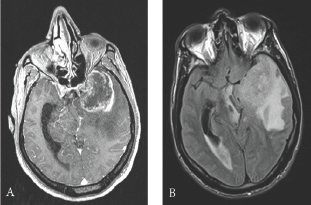

Brain MRI revealed left temporal heterogeneously enhancing lesion, voluminous with signs of engagement. The radiological profile was highly suggestive of glioblastoma (Figure 1).

Figure 1: Preoperative contrast-enhanced, axial T1- weighted magnetic resonance images: (A) internal temporal and temporo-polar mass measured at 35 x 47 mm. Heterogeneously enhanced lesion with central necrosis (B) important perilesional oedema with left ventricular enlargement and left temporal engagement and mass effect on the left midbrain and on the chiasma.